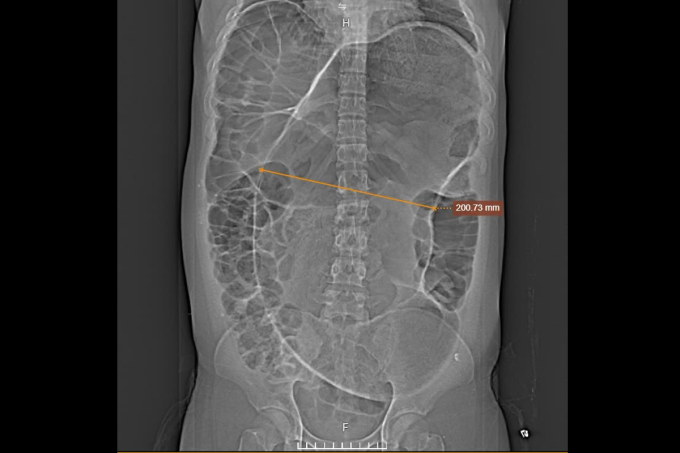

Trước đó, Minh bị táo bón điều trị bằng thuốc và đặt ống thông hơi, ba tháng sau bụng phình to gây khó thở, đau bụng, không ăn uống được phải truyền dinh dưỡng. Kết quả chụp CT 1975 lát cắt tại Bệnh viện Đa khoa Tâm Anh ghi nhận xoắn đại tràng sigma (đoạn cuối của đại tràng), cuộn tròn mạch máu mạc treo và quai ruột đại tràng sigma đường kính 20 cm – to hơn gần 7 lần bình thường, lòng ruột chứa đầy khí, cặn bã, thành ruột mỏng.

Chụp cắt lớp vi tính cho thấy đoạn đại tràng căng to (mũi tên vàng). Ảnh: Bệnh viện Đa khoa Tâm Anh